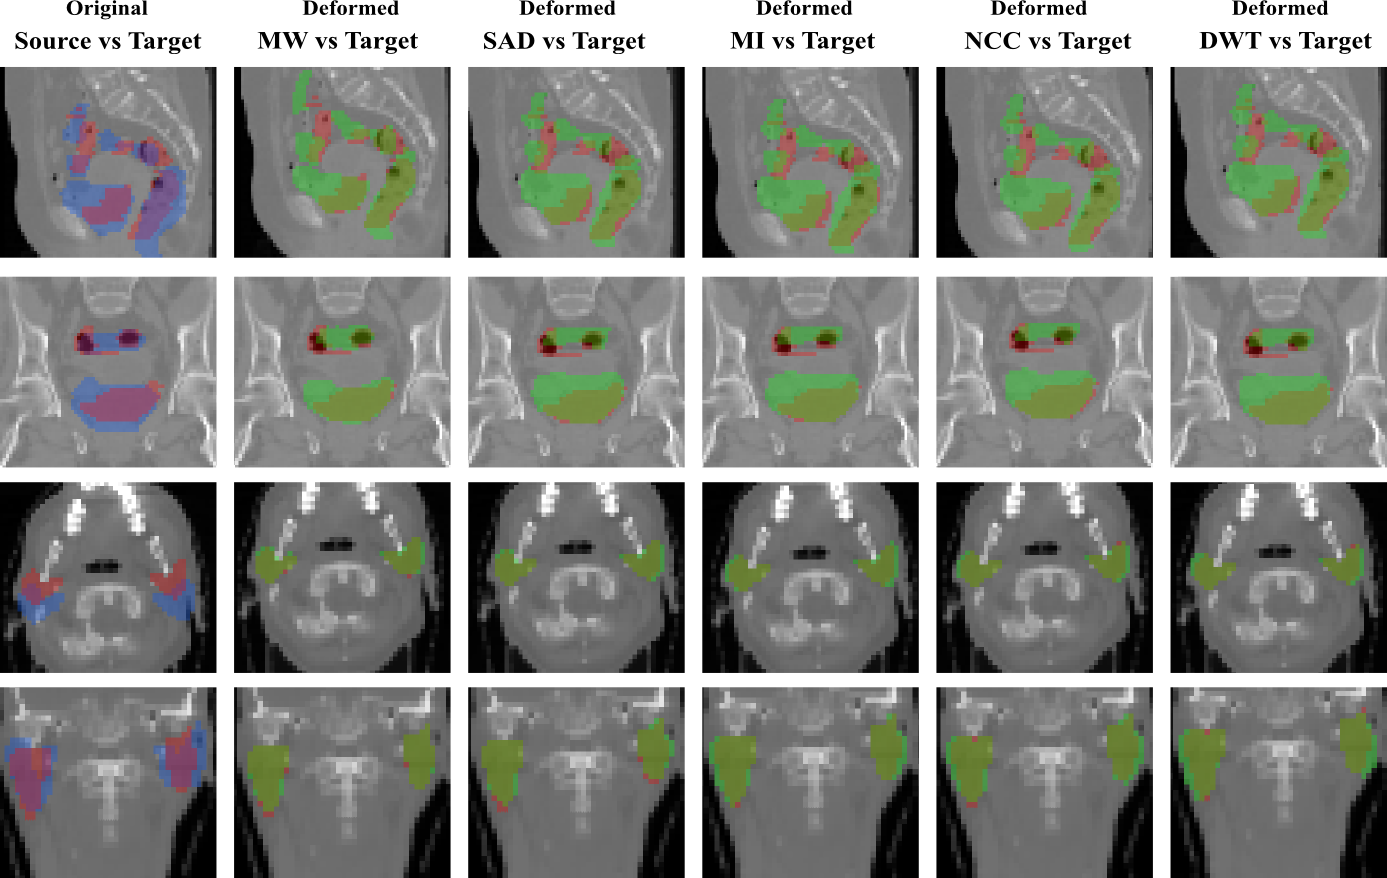

Figure 3: Overlapping of the segmentation masks in different views for one registration case from RT Abdominal (first and second rows) and RT Parotids (third and fourth rows) datasets. The first column corresponds to the overlapping before registration between the source (in blue) and target (in red) segmentation masks of the different anatomical structures of both datasets. From second to sixth column, we observe the overlapping between the warped source (in green) and the target (in red) segmentation masks, for the multi-weight algorithm (MW) and for the single metric algorithm using sum of absolute differences (SAD), mutual information (MI), normalized cross correlation (NCC) and discrete wavelet transform (DWT) as similarity measure.

RT Parotids It contains 888 CT volumes of head, obtained from 4 different patients, 2 volumes per patient. The volumes are captured in two different stages of a radiotherapy treatment in order to estimate the radiation dose. Right and left parotid glands were segmented by the specialists in every volume. The dimensions of the volumes are 56×62×5356625356\times 62\times 53 voxels with a physical spacing of 3.453.453.45mm, 3.453.453.45mm, and 444mm, in x, y, and z axes, respectively. We generated 888 pairs of source and target volumes using the given dataset. Notice that, while generating the source and target pairs, we did not mix the volumes coming from different patients. We split the dataset into train and test, and cross validated the hyper-parameters C𝐶C and α𝛼\alpha on the train dataset. The average result on the test dataset are shown in the Figure 5.a, while qualitative results can be found in Figure 3.

Figure 2 shows the examples of the slices from the 3D3𝐷3D volumes corresponding to each dataset. In figures 3 and 4 we include some qualitative results on the three challenging datasets in order to highlight the effects of learning the weights of different metrics. In the first one (figure 3), we present the overlapping of the segmentation masks in different views for one registration case from RT Abdominal and RT Parotids datasets, using single and multi-metric approaches. The observed results are coherent with the numerical results reported in figures 5.a and b. We observe that multi-weight algorithm gives a better fit between the deformed and ground truth structures than the rest of the single similarity measures, which are over segmenting most of the structures showing a poorer registration performance. In the second graph (figure 4), we include results for the IBSR dataset. Extreme values (which mean high differences between the images) correspond to blue and red colors, while green indicates no difference in terms of intensity. Note how most of the big differences observed in the first column (before registration) are reduced by the multi-weight algorithm, while some of them (specially in the peripheral area of the head) remain when using single metrics.